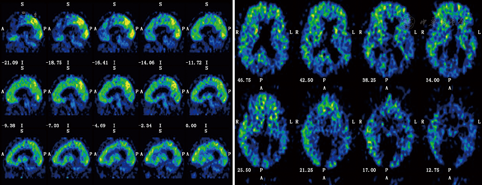

患者行11C-PIB PET显像,视觉分析显示对照组注射PIB 45 min后,皮质、皮质下核团、脑桥、小脑放射性活性基本上已清除。该患者双侧额顶枕叶、颞叶外侧皮质、扣带回/楔前叶等部位放射性活性清除减慢(图3)。基于体素水平自动化分析显示PCA患者PIB平均摄取值在顶下小叶、颞叶外侧皮质、额中回、前额内侧皮质、枕叶、后扣带回/楔前叶、辅助运动区、颞上回、纹状体均增高。

PCA在已诊断痴呆的病例中占5%,在新诊断的痴呆病例中约占4%[5]。截至2010年,中国痴呆人数已逾千万,65岁人群痴呆发病率为9.87%[6]。由此推算,我国可能有超过500 000例的PCA患者,且该数量仍在快速增加,但国内有关PCA的神经影像学和神经病理学研究鲜有报道[7]。受限于我国国情,有关PCA的神经病理学研究开展相对困难,但随着18F-FDG PET和11C-PIB PET显像技术的不断发展,神经影像学对PCA的诊断作用日益凸显。本例患者头颅MRI提示顶枕叶萎缩明显,颞叶内侧萎缩不明显,这些表现有利于识别PCA并与典型阿尔茨海默病(Alzheimer′s disease,AD)相区别。但仅有头颅MRI证据是远远不够的,特别是疾病早期阶段,18F-FDG PET和11C-PIB PET通过显示脑代谢及β-淀粉样蛋白(Aβ)沉积,可为临床早期诊断PCA提供结构影像学之外的客观、独立证据[8]。FDG-PET功能成像研究提示PCA患者存在一致的顶枕区及后颞部皮质代谢减低[9]。Whitwell等[10]利用基于像素的形态测量学和质子磁共振波谱分析技术进行对照研究发现,PCA主要累及双侧枕叶、顶叶和颞叶后部,以右侧更明显。本例患者18F-FDG PET呈现较典型的右侧为著的颞顶枕联合区代谢减低,尤以右侧减低明显,与文献报道一致,提示PCA可能以右侧皮质变性为主。根据文献报道,PCA的病因包括AD、路易体痴呆、皮质下胶质细胞增多症、皮质基底节变性等,其中AD是最常见的病因。本例患者11C-PIB PET亦显示额颞顶枕皮质的Aβ沉积,与典型AD患者脑组织Aβ分布无明显差异,但关于PCA和AD患者老年斑和神经原纤维缠结分布的研究结果并不一致,有研究显示PCA和AD患者老年斑和神经原纤维缠结的分布不同[11],提示PCA可能为AD的一种特殊类型。